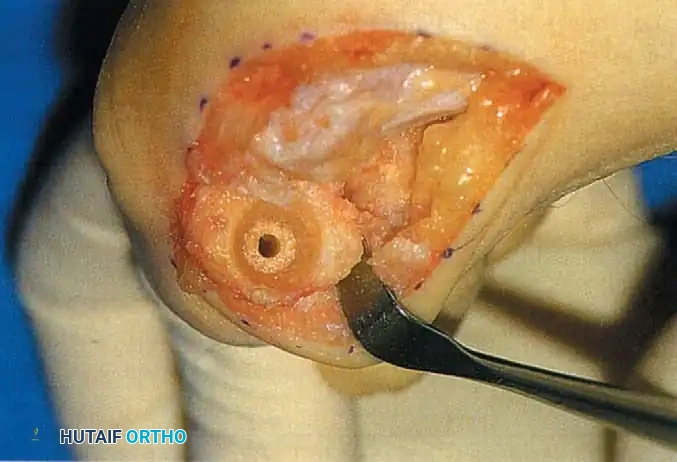

• Using a Freer elevator or a small osteotome for its strength, mobilize the fi bular sesamoid (Fig. 78-31A to C). This may be diffi cult in elderly patients with signifi cant deformity and adherence of the sesamoid to the metatarsal head. Lift the metatarsal dorsally for exposure (Fig. 78-31D and E).

Fig. 78-31 Excision of fi bular sesamoid in modifi ed Keller procedure. With base of proximal phalanx removed and medial eminence excision, exposure of fi bular sesamoid is not as diffi cult from medial incision. A, Operative photograph showing elevation of fi rst metatarsal with strong two-tooth retractor and use of small osteotome to mobilize fi bular sesamoid and lateral capsuloligamentous (frequently contracted) structures. Osteotome is between metatarsal head and lateral sesamoid. When mobilization of fi bular sesamoid is complete, entire sesamoid is visible for excision. Note chondromalacia of tibial sesamoid articular surface medial to osteotome. B, Fibular sesamoid has been excised, and lateral capsular structures and conjoined tendon (in forceps) have been released. Neurovascular bundle to lateral side of hallux is adjacent to these structures. C, Diagrammatic representation of modifi ed Keller procedure. By excising fi bular sesamoid, valgus moment of conjoined tendon of fl exor hallucis brevis and adductor hallucis no longer pulls fl exor hallucis longus tendon laterally (carrying hallux with it) through capsulosesamoid plantar plate and pulley system. D, Metatarsal head must be lifted dorsally to excise fi bular sesamoid under direct vision. E, Note exposure of fi bular sesamoid after mobilization of metatarsal head. Continued